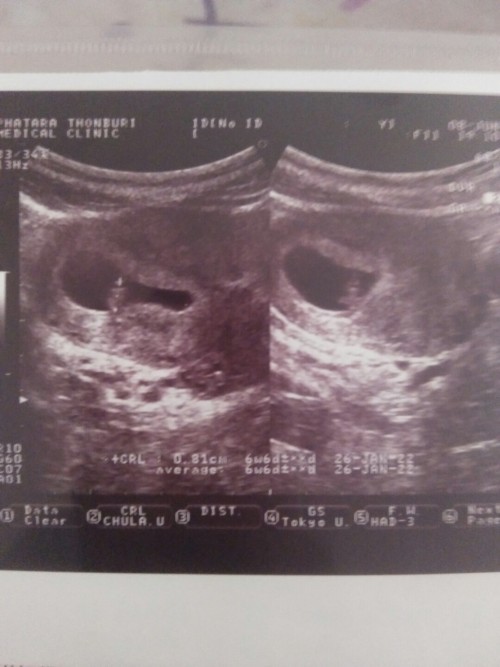

ซาวด์ตอน 5 w 2 d ค่ะ เจอแต่ถุงน้ำคร่ำยังไม่เห็นตัวอ่อน อยากทราบแม่ๆท่านอื่นเป็นแบบนี้ไหมคะ แอบกังวลค่ะ #ท้องแรกค่ะ

เป็นเหมือนกันค่ะ 6w เจอแต่ถุงตั้งครรภ์ เจอน้องตอน 8w